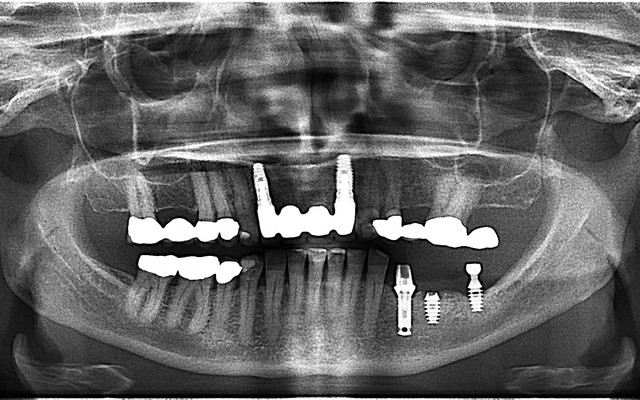

A panoramic radiograph is a panoramic scanning dental X-ray of the upper and lower jaw. It shows a two-dimensional view of a half-circle from ear to ear.

The X-rays use small amounts of radiation. Panoramic X-rays show a broad view of the jaws, teeth, sinuses, nasal area, and temporomandibular (jaw) joints. These X-rays show problems such as impacted teeth, bone abnormalities, cysts, solid growths (tumors), infections, and fractures